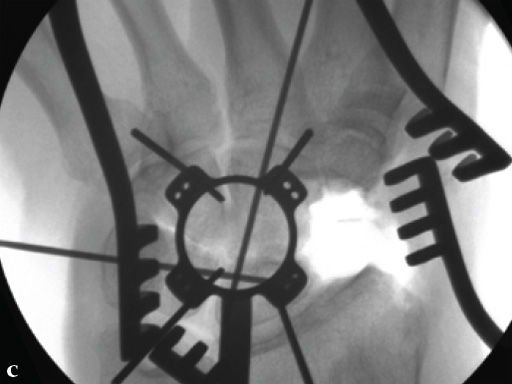

Fig 3ab Bone debridement. Guide positioning and fixation.

Fig 3c Bone debridement. Guide positioning and fixation.

Fig 4c Once the carpal junctions have been putting closer by the new reduction-compression guide, reaming is done.